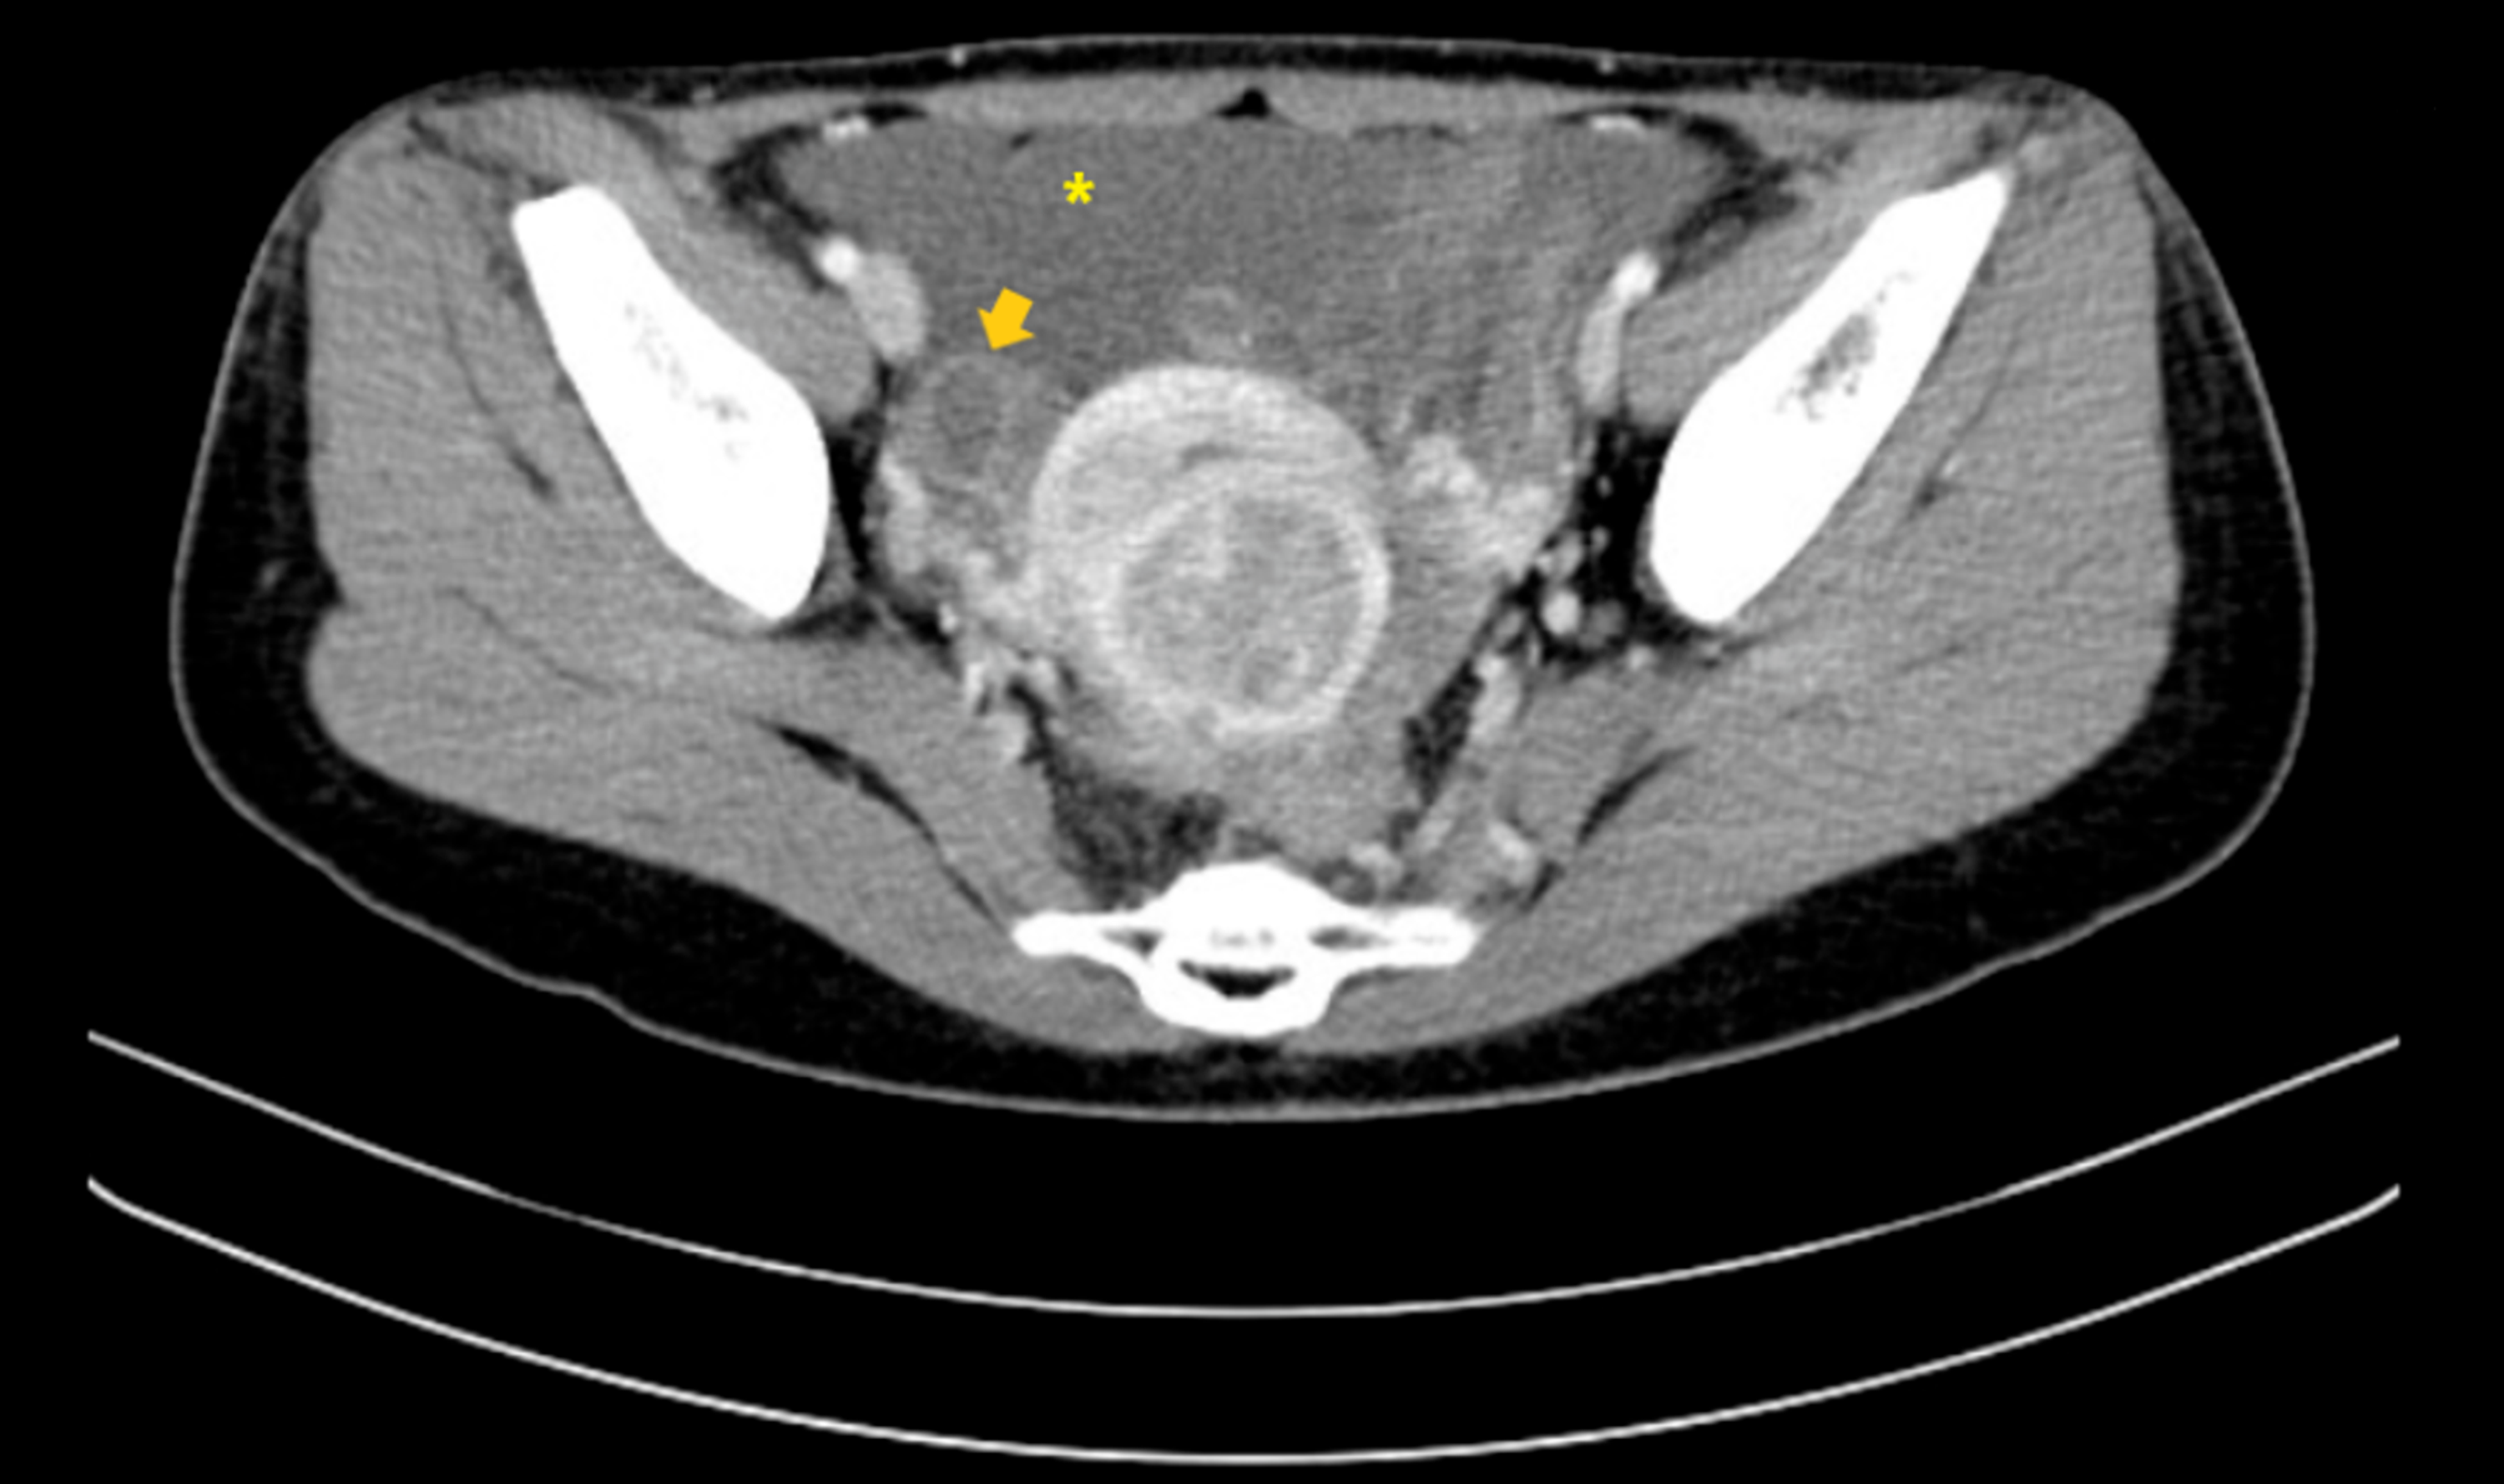

A 34-year-old Taiwanese nulligravida woman presented to the outpatient department with a one-year history of irregular dysmenorrhea that was 5/10 in severity. She had no other associated complaints such as weight loss, anorexia, dyspareunia, urinary changes, or heavy menstrual bleeding. On further probing, the patient revealed having mild bloating that did not cause discomfort. Her menstruation occurred at regular monthly intervals. On physical examination, she had clear breath sounds and mildly distended flanks. Pelvic examination showed a corpus enlarged to 8-10 weeks' size without adnexal masses or tenderness. Fullness at the cul-de-sac was palpated. Pelvic ultrasound revealed multiple small leiomyomas with massive ascites and a heterogeneous right ovarian tumor. A CT scan showed a multicystic right ovary with soft tissue seeding to bilateral paracolic gutters, omentum, and recto-uterine pouch, with massive ascites (Figures 1, 2). CA-125 was elevated (819.1 U/mL). With the working diagnosis of a possible malignant ovarian tumor, laparotomy was performed with staging surgery in mind.